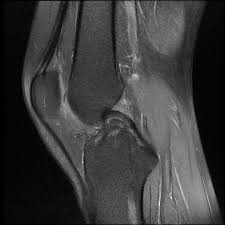

Meniscal tear can be well appreciated on an mri. In humans they are present in the knee, wrist, acromioclavicular, sternoclavicular, and temporomandibular joints; In other animals they may be present in other joints.

During knee flexion, the menisci are pulled dorsally by the femoral condyles.

Circle of villis angiogram anatomy mri. The posterior horn is always larger than the anterior horn. Meniscus rupture can occur with a sharp movement in the lateral direction, or in a direction that goes beyond the. Magnetic resonance (mr) imaging of the knee and ankle is playing an increasingly important role in the detection, diagnosis and prognosis of these injuries and their associated complications.